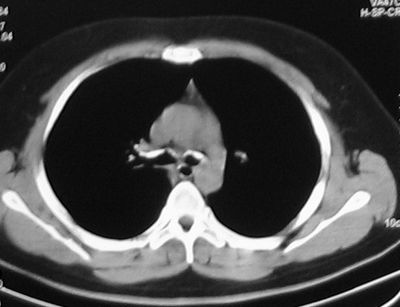

RP的胸部影像学检查 胸片显示可有呼吸道感染、肺不张及肺炎改变。CT由于具有较高的空间及密度分辨率,可以较好的显示气管及支气管病变范围、管壁厚度、管腔狭窄程度及纵膈淋巴结肿大,所以对于早期发现本病,改善患者的预后,有较高的价值。特别是CT三维重建可清楚显示管腔一系列临床病理改变。RP的主要CT表现为气管及主支气管管壁的增厚及管腔的狭窄。大气管受累包括胸廓外及胸廓内的部分,部分向上延伸可累及喉部软骨。在急性期,由于炎性水肿及肉芽组织增生,可导致气道壁的广泛增厚,其特征为以大气管的前、侧壁增厚为主,而其后壁的膜部大致正常。增厚的大气管的内、外轮廓比较光整。长期反复发生慢性炎症,软骨破坏,可逐渐出现程度不等的管壁钙化[7-8]。(见后附图)

图1:大气管前侧壁钙化

图2:左、右主支气管前壁钙化

图3:大气管壁前侧壁明显增厚、管腔狭窄